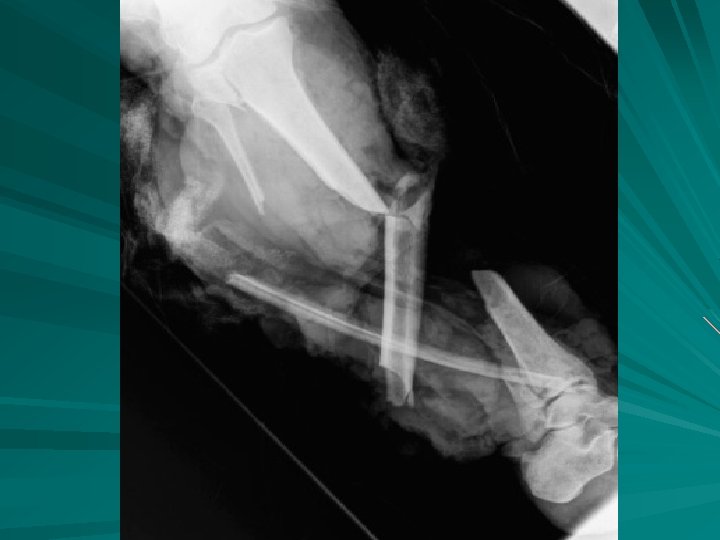

Compound Fx of Femur

Zoomed lower pelvis demonstrating multiple fractures (arrows).